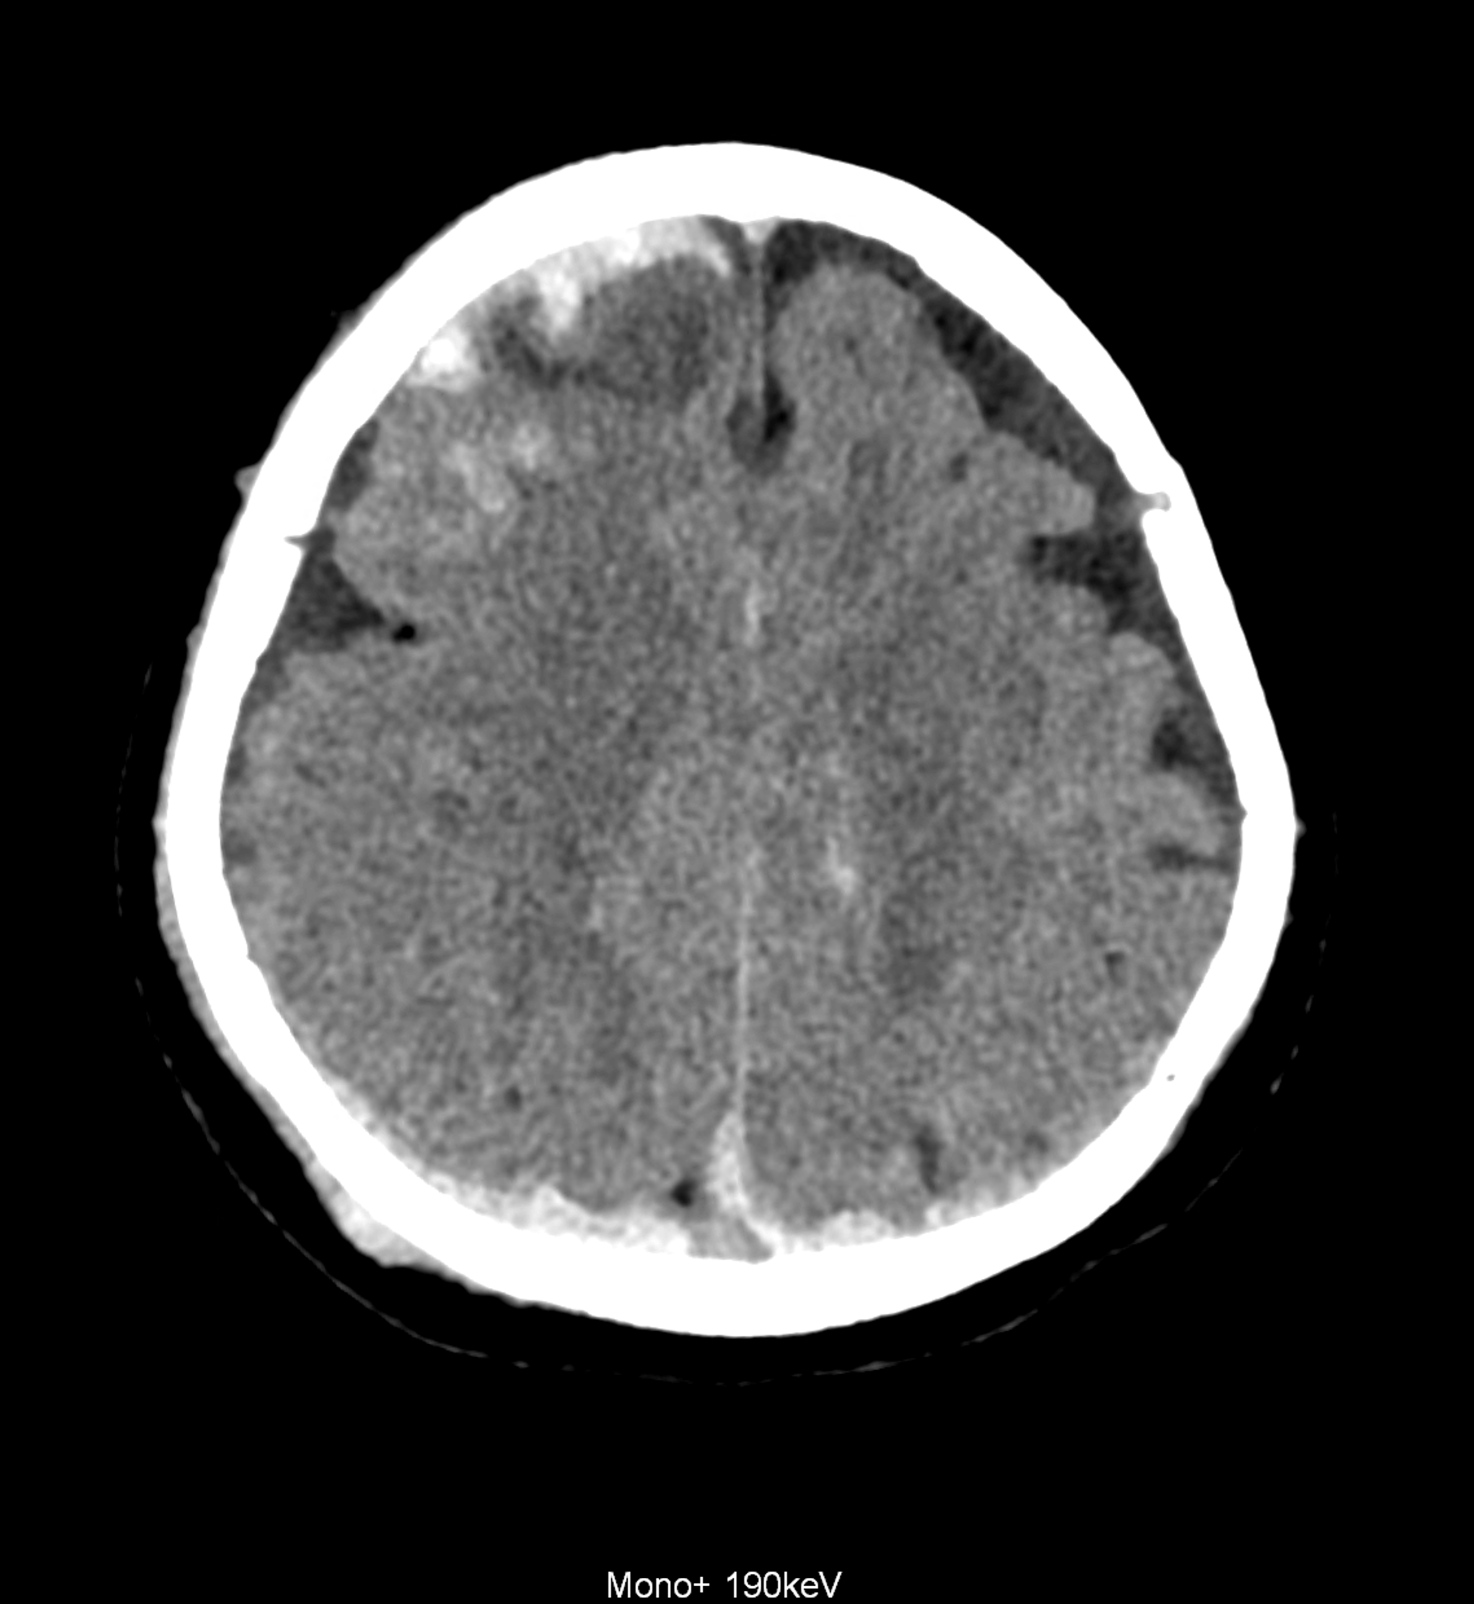

Bleeding is characterized by different absorption characteristics than healthy brain tissue (both gray and white matter) and cerebrospinal fluid. Due to the higher proportion of proteins with amino acids with disulfide bonds, the signal intensity increases at higher energies, making it possible to use monoenergetic imaging at energies above 140 keV, and/or virtual non-contrast. The hemorrhage then becomes more hyperdense, while the rest of the brain tissue acquires a uniform low signal. In addition to bleeding, areas of extracellular fluid of vasogenic origin are also imaged, i.e., in areas around contusion-type brain tissue injuries.

An example of the use of spectral imaging in complex brain injury, where contusions, diffuse axonal injury, subarachnoid hemorrhage, subdural hemorrhage, and blood in the ventricular system are present.

comparison of the images with the energies of monoenergetic reconstructions 40 keV, 67 keV (standard conventional reconstruction), 190 keV and virtual non contrast (VNC)